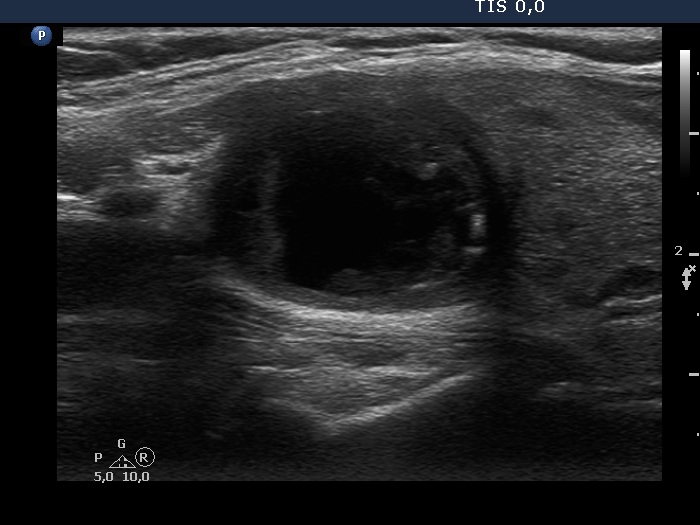

Ultrasonography. The thyroid was echonormal. There was a mixed moderately hypoechogenic-cystic nodule in the right lobe. The lesion presented various intranodular hyperechogenic granules including back wall figures, non-specific granules and a few typical comet-tail artifacts. There were other, difficult-to-classify bright granules. The latter could be either comet-tail artifacts or microcalcifications. There were several moderately hypoechogenic lesions in the left lobe.

Comments. This case illustrates the difficulty of distinguishing comet-tail artifact from microcalcification. The relevance of this differentiation lies in the consequences, the former is found almost always in benign lesions while the presence of microcalcifications increases the likelihood of papillary carcinoma.